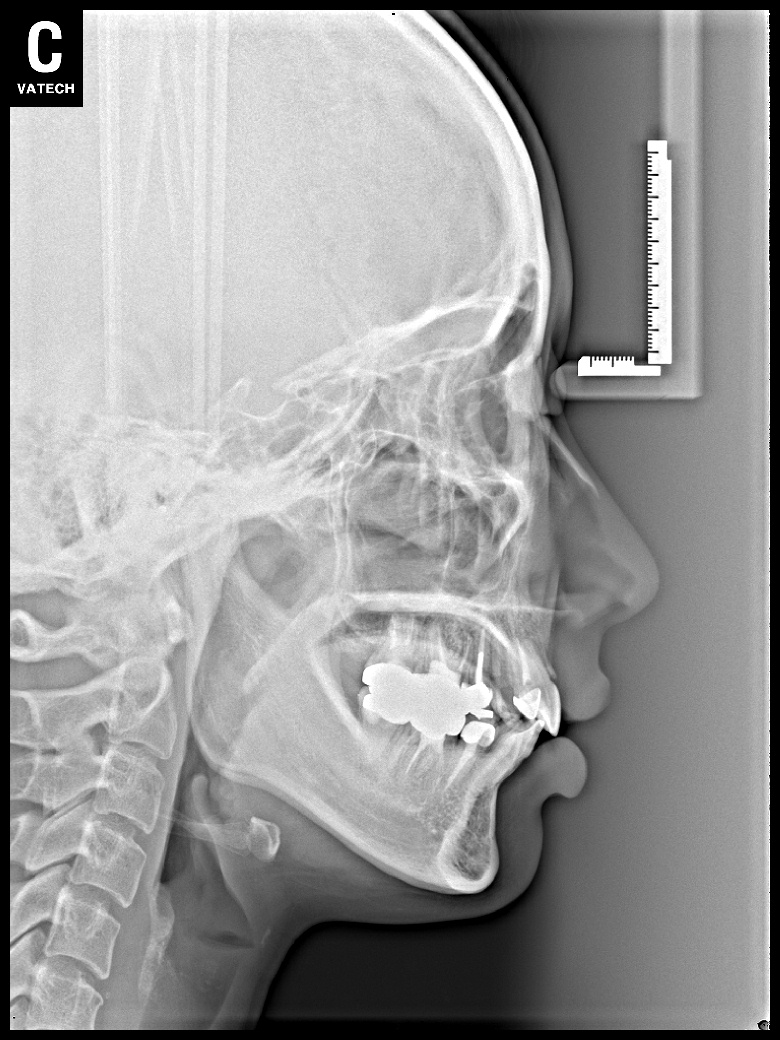

치료 후 사진입니다.